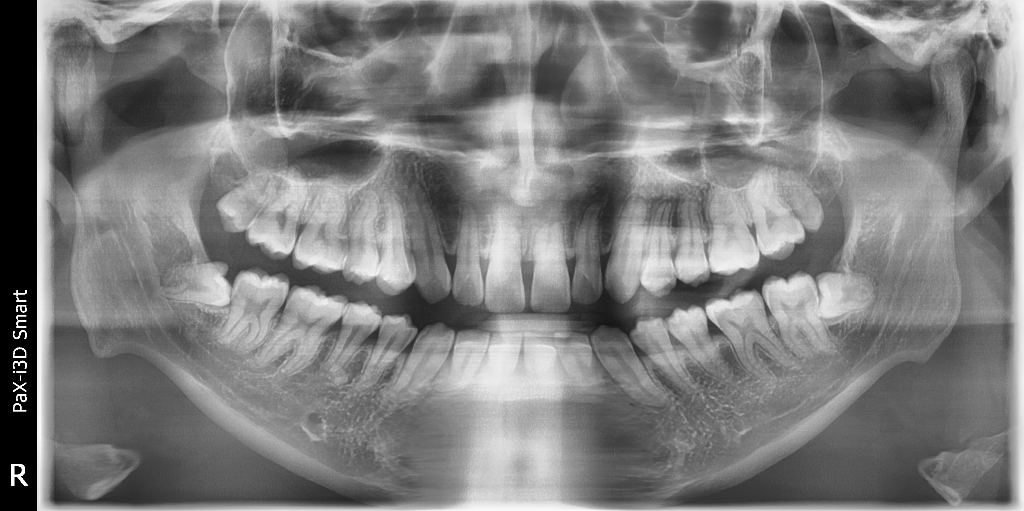

어금니 끝부분에 검은색으로 뭔가 나있는데 이거 뭔가요?

이게 무엇인지 알려주셨으면 감사하겠습니다 혹시 사랑니가 썩게된건지 참고로 가끔 이 부위가 통증을 일으킵니다. 파노라마 사진도 함께 첨부해서 보내드리니 친절한 답변 부탁드려요

방사선 사진상 사랑니가 충치가 생긴 것 같지는 않으나 해당 부위 사랑니의 부분 매복으로 인해 잇몸이 벌어져 있고 잇몸도 부어있는 상태입니다.

부분 매복 사랑니는 향후 문제를 일으킬 여지가 많으므로 예방적으로 발치를 권합니다.